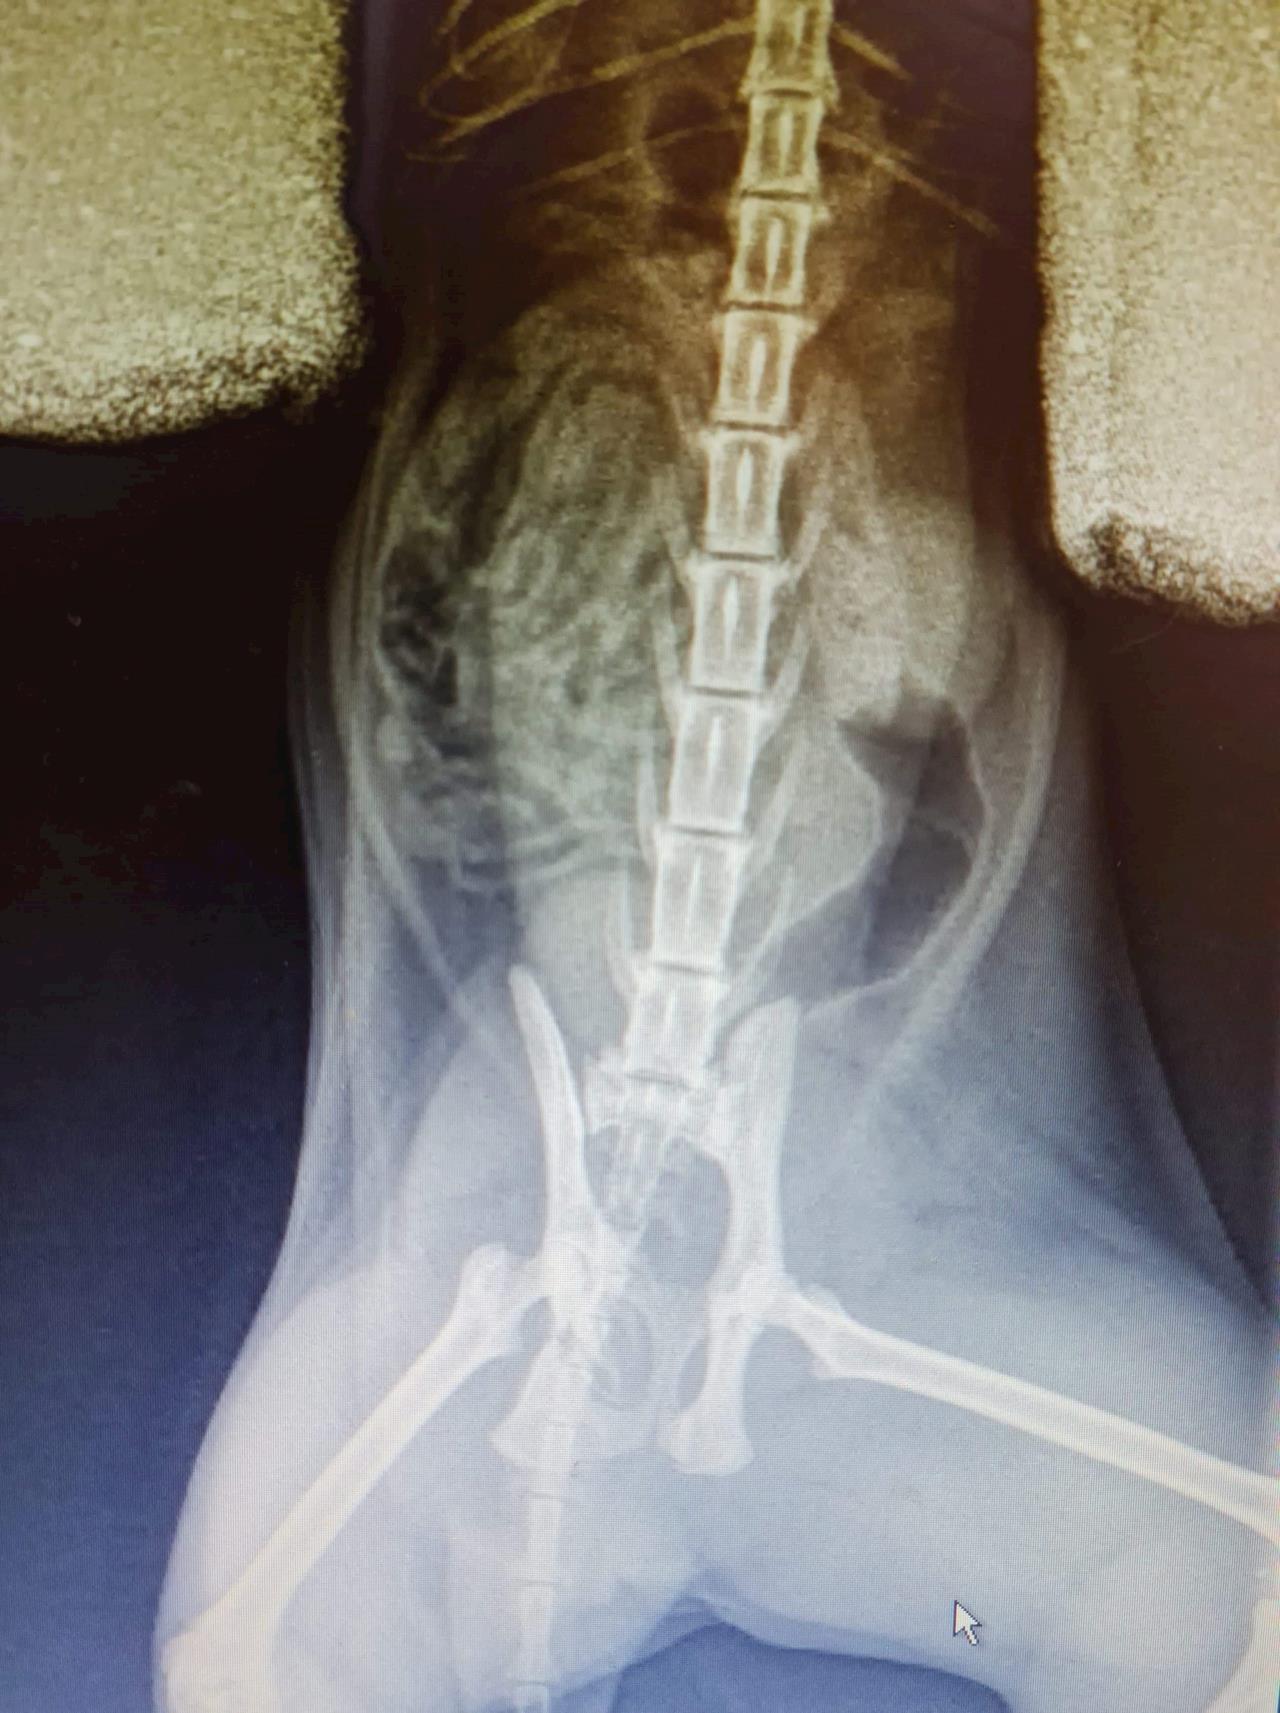

Main image

Went to visit Bernie today at Karorir Veterinary Clinic. X-rays show her pelvis is worse than thought in terms of narrowing, plus 2 fractures they could see. The left pelvic bone is fine, but the right one is angled very narrow. It means a hit and run is likely what caused the injuries. She has been put on pain medication and anti inflamatories, but they were unable to get her on a drip or properly fix a catheter.

A request with the Massey University Animal Surgery department was made today, and they will ring me with an update on the procedure from here sometime tomorrow. They will do further x-rays to make sure there aren't any joint fractures.